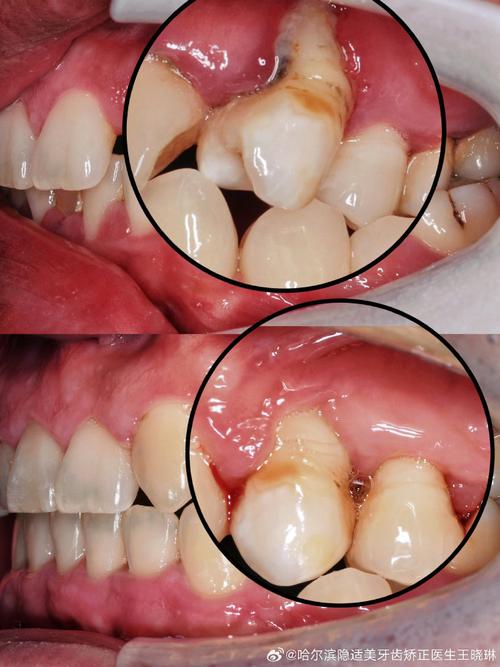

牙周组织(包括牙龈、牙周膜、牙槽骨等)是牙齿赖以生存的土壤,若存在牙周炎症(如牙龈炎、牙周炎),牙槽骨会吸收、牙齿松动,此时强行正畸可能导致骨吸收加剧、牙齿脱落等严重后果,牙周刮治作为牙周治疗的基础手段,通过龈下刮治和根面平整,彻底清除牙龈下方的牙结石、菌斑以及被感染的牙骨质,消除炎症介质,为牙周组织的再生创造条件。

临床数据显示,未经牙周治疗的正畸患者,其牙周炎复发风险是牙周治疗后再正畸的2-3倍,对于探诊深度(PD)>5mm、附着丧失(CAL)≥3mm的中重度牙周炎患者,若直接正畸,牙齿移动过程中机械刺激可能进一步破坏已受损的牙周支持组织,导致牙槽骨水平吸收加速,正畸前必须通过牙周刮治将炎症控制在可接受范围内,即达到“牙周稳定状态”:牙龈无红肿出血、探诊深度≤3mm、牙槽骨吸收停止(通过X线片确认)。